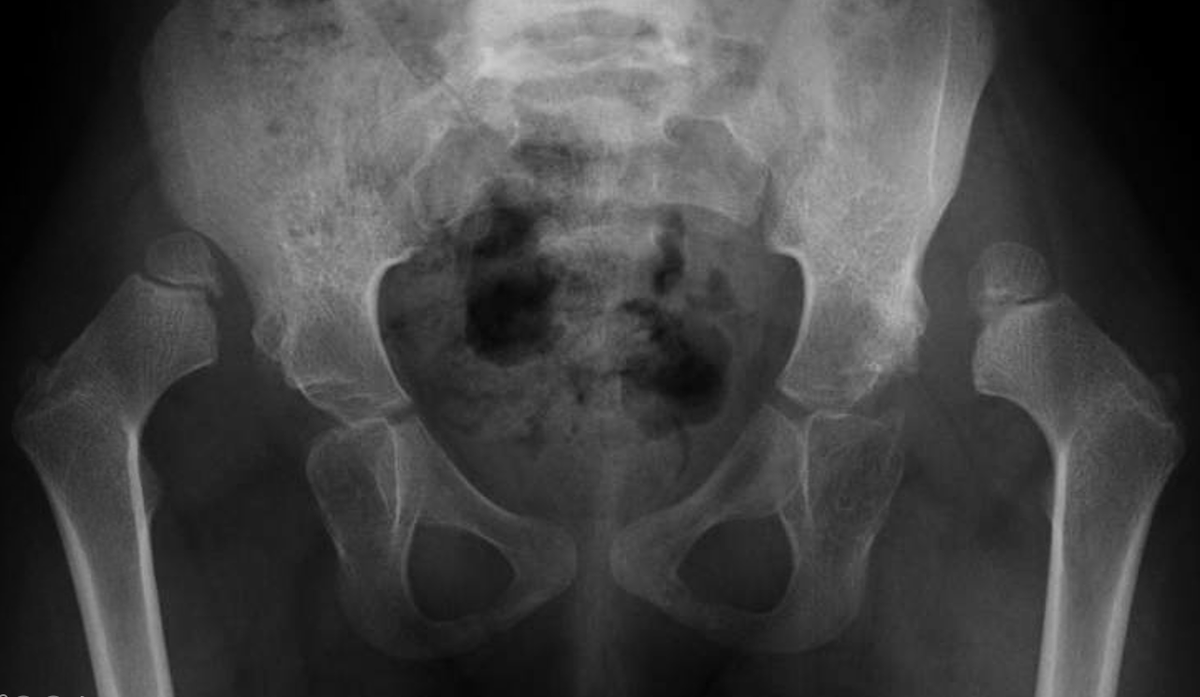

في الصورتين القادمتين تبيان لشكل مفصل الورك عند الأطفال في السنة الثانية من العمر، الأولى تبين الوضع الطبيعي لهذا المفصل الهام والثانية توضح مشكلة الخلع الولادي الكامل لمفصل الورك

هذه الحقائق المزعجة عن صعوبة اكتشاف الخلوع الولادية لمفصل الورك عند المواليد تجعل غالبية المصابين بهذه المشكلة لا يتم تشخيصهم حتى يبدأون بالمشي ويظهر للمقربين من هذا الطفل العرج الواضح في مشيته بسبب الخلع في مفصل الورك.

الجواب ، الخلع الولادي لا يمنع الطفل من المشي ولكنه يؤدي إلى مشية غير طبيعية (عرج) ...

إذا كان الطفل مصابا بالخلع الولادي في كلا الوركين، فإن العرجة لا تكون واضحة جدا وهو الأمر الذي قد يتسبب في تأخير التشخيص لفترة أطول..

أما الخلع في جهة واحدة عادة يكون الاشتباه فيه كبيرا عندما يبدأ الطفل خطواته الأولى ...